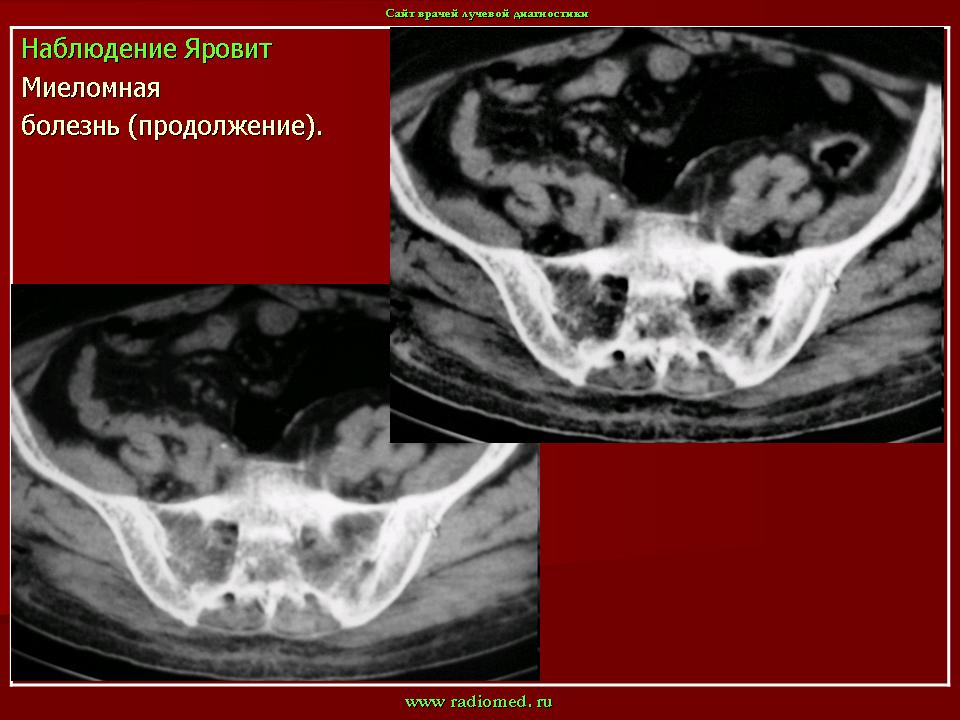

продолжение.

1.p.slayd148.jpg1.mm_.slayd259.jpg